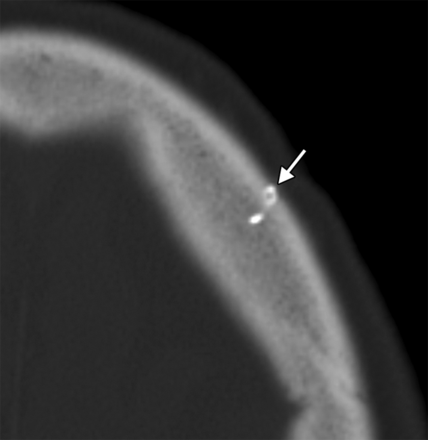

Implantation of gold and platinum eyelid weights into the upper eyelid is a static reanimation procedure for treating lagophthalmos.2 Although gold weights are more commonly used, platinum weights have a thinner profile and therefore offer an increased aesthetic benefit.3 Available eyelid implant designs include curved metal sheets with holes to permit anchoring with a suture (Fig 3) and flexible metal chains. In-growth of fibrous tissue through the holes also helps secure the weight in position. Eyelid weights are secured to the superficial aspect of the upper eyelid tarsal plate. The eyelid weights generally produce considerable streak artifacts on CT, which can obscure surrounding structures (Fig 4). Platinum and gold eyelid weights are considered MR imaging–compatible up to 7T4,5 but may cause local field inhomogeneity (Fig 5). Complications related to eyelid weight implantation include suboptimal eyelid contour, infection, allergic reaction, migration, and extrusion.6

Eyelid weight. Axial CT image shows extensive streak artifacts related to the left eyelid weight, which obscures surrounding structures.